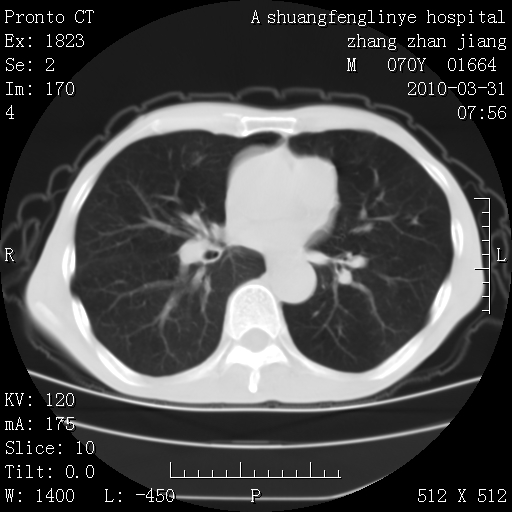

标题: CT25450:肺结核?

支持,不过左肺中叶那个像陈旧病变的结节要不要单报一下,在图上没看到钙化单报一下放心啊

双上肺继发型tb并左上空洞形成,主动脉冠脉钙化。

支持:继发性肺结核伴空洞形成!建议纤支镜检查待出外周围型肺癌可能!

1)两肺上叶继发性肺结核并左肺上叶空洞形成。2)冠状动脉及主动脉钙化。